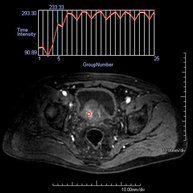

Prova diagnòstica no invasiva que consisteix en l'obtenció d'imatges d'alta definició anatòmica de la pelvis mitjançant l'ús d'un camp electromagnètic i ones de ràdio (amb un emissor i un receptor). No utilitza radiació ionitzant. Es realitza per a l'estudi de patologies d'úter, d'ovari, de trompes i de vagina, ja siguin d'origen tumoral, inflamatori o vascular. També permet valorar les estructures adjacents localitzades a la pelvis i la identificació de les seves alteracions. De vegades és necessari l'ús de contrast intravenós (Gadolini) per caracteritzar les lesions. - RM Pelvis masculina

Prova diagnòstica no invasiva que consisteix en l'obtenció d'imatges d'alta definició anatòmica de la pelvis masculina mitjançant l'ús d'un camp electromagnètic i ones de ràdio (amb un emissor i un receptor). No utilitza radiació ionitzant. No requereix preparació prèvia. En algunes ocasions necessita l'ús de contrast paramagnètic (Gadolini) per caracteritzar les lesions. Aquesta prova permet valorar òrgans com la bufeta urinària, la unió entre els urèters i la bufeta, la pròstata, les vesícules seminals, la uretra i els ossos de la pelvis, entre d'altres. - RM de Fetge